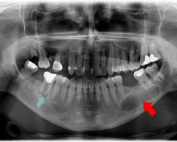

چه زمانی دندان قابل نگه داشتن نیست؟

یکی از سخت ترین تصمیمات در دندانپزشکی، تشخیص مرزی است